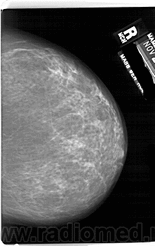

Со старением железистая ткань постепенно исчезает: прозрачность жировой ткани становится преобладающей с несколькими каркасами, связанными с опорными волокнистыми структурами.

Жирная (не плотная) грудь

Умеренно плотная грудь

Плотная грудь

Маммограммы представляют собой изображения структур, проецируемых на плоскость: плотная грудная маммограмма, следовательно, состоит из многих других структур, которые необходимо проанализировать, чем более жирная, пустая грудь. По этой причине диагностировать рак молочной железы труднее для моложе, чем для пожилых женщин.

Нажмите на миниатюрные картинки, чтобы получить увеличенный размер.